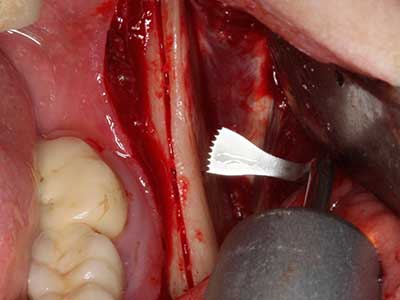

Abb. 18: Präparation eines Kortikalis-Deckels mit der Piezo-Knochensäge (Piezomed, W&H).

Abb. 19: Operationssitus nach Neurolyse und Osteomentfernung.